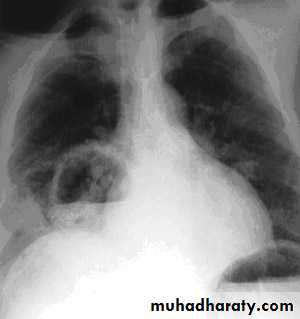

Chest X-ray show multiple lung abscess

Staphylococcus pneumonia

Coexistent debilitating illness and often preceded by influenza. Radiographic features include multilobar shadowing, cavitation, pneumatoceles and abscesses. Dissemination to other organs may cause osteomyelitis, endocarditis or brain abscesses. Mortality up to 30%.